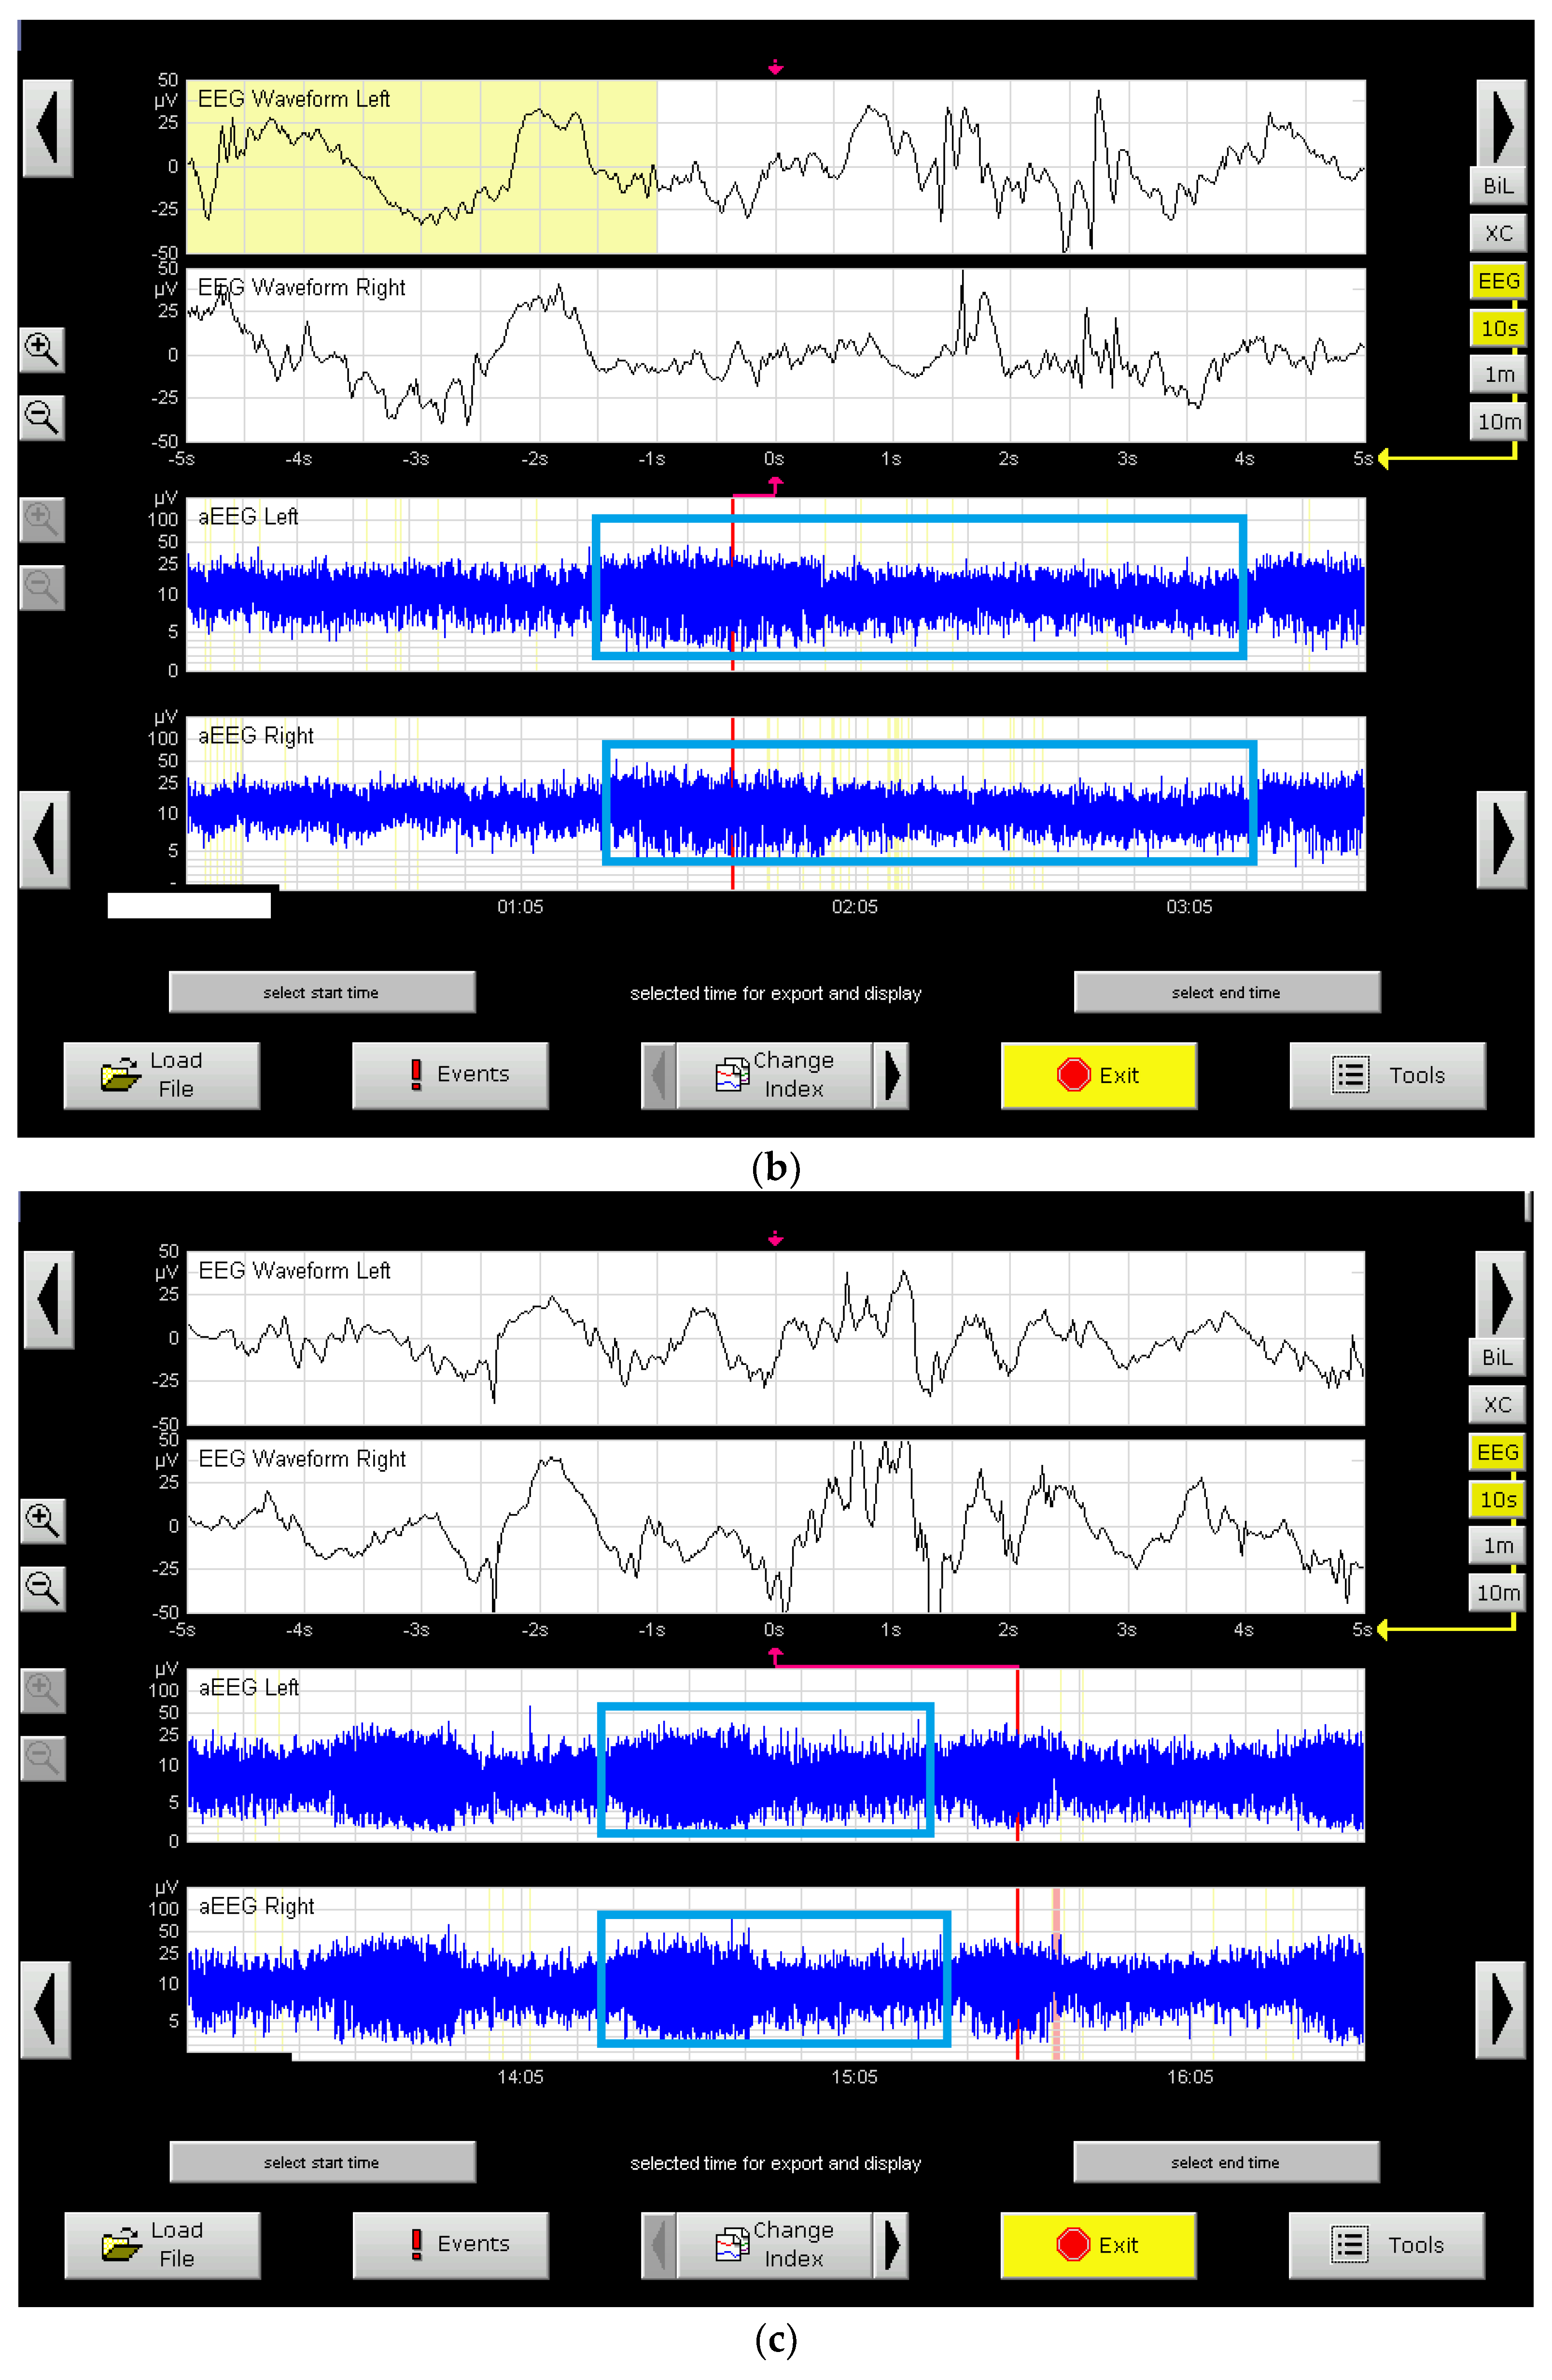

- Halberg, B.; Grossmann, K.; Bartocci, M.; Blenow, M. The prognostic value of early aEEG in asphyxiated infants undergoing systemic hypothermia treatment. Acta Paediatr. 2010, 99, 531–536. [Google Scholar] [CrossRef]

- Massaro, A.N.; Tsuchida, T.; Kadom, N.; El-Dib, M.; Glass, P.; Baumgart, S.; Chang, T. aEEG Evolution during Therapeutic Hypothermia and Prediction of NICU Outcome in Encephalopathic Neonates. Neonatology 2012, 102, 197–202. [Google Scholar] [CrossRef]

- Osredkar, D.; Toet, M.C.; van Rooij, L.G.M.; van Huffelen, A.C.; Groenendaal, F.; de Vries, L. Sleep–wake cycling on amplitude-integrated EEG infull-term newborns with hypoxic–ischemi encephalopathy. Pediatrics 2005, 115, 327–332. [Google Scholar] [CrossRef]

- Chalak, L.; Hellstrom-Westas, L.; Bonifacio, S.; Tsuchida, T.; Chock, V.; El-Dib, M.; Massaro, A.; Garcia-Alix, A. Bedside and laboratory neuromonitoring in neonatal encephalopathy. Semin. Fetal Neonatal Med. 2021, 26, 101273. [Google Scholar] [CrossRef]